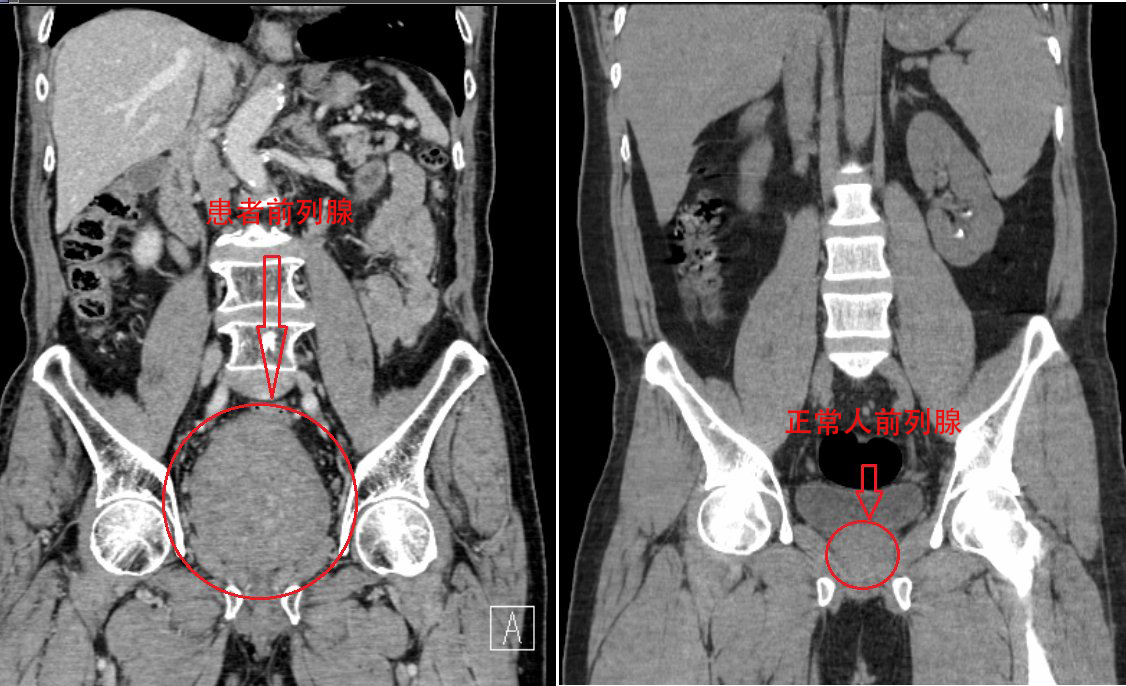

正常前列腺重量约20g,而李大爷的前列腺重量达到惊人的400g!增重近20倍。增生达100g以上已算重度增生,近400g更是罕见。然而,能解决李大爷痛苦的方法只有两种,一种是通过膀胱造瘘或者长期留置尿管,这种方案虽然简单,但是今后的生活及护理极不方便,会给患者造成很大的心理负担。另一种就是将增生的前列腺用我院最先进、最成熟的钬激光“切掉”,最终李大爷选择手术。